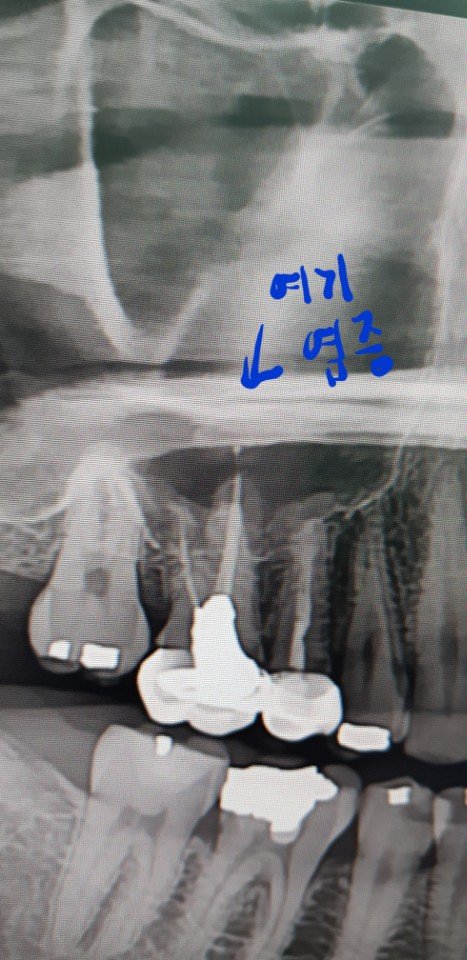

치아 위에 예전 치료하다 생긴 염증으로 인해 농이 찬거라서 바로 치아 발치 후 임플란트나 브릿지를 해야한다 하셨어요

여기에 염증 있어서 조금만한 점인데 신경치료나 마취치료등 잘못으로 인한거라던데 언제 한건지 아냐하셔서 모른다 하니 무조건 뽑아야한다셨어요

비정상

정상